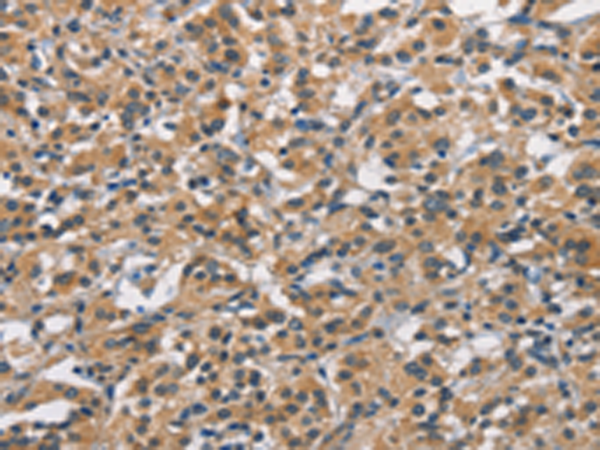

分类: 科研抗体货号: P11181别名: AMD; SAMDC; ADOMETDC应用: IHC反应种属: Human, Mouse, Rat